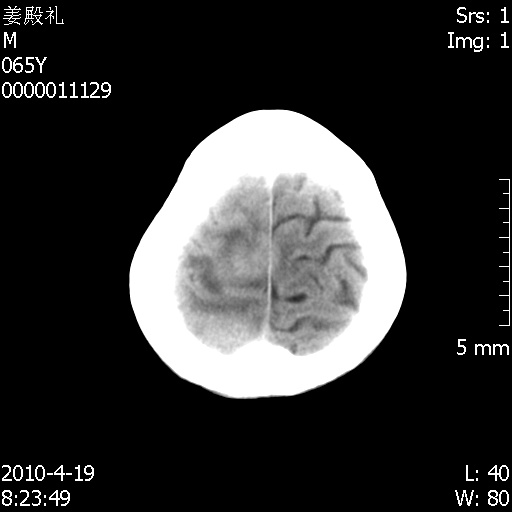

老年男性,突发左下肢无力1天,其余有价值的检查都没有。平扫ct值大约60hu,增强后ct值没什么改变,请大家讨论一下这个病例是什么?说明诊断理由。

左小脑、右大脑顶叶多发圆形高密度病灶,其周环状低密度影。考虑多发脑出血。隔期观察。